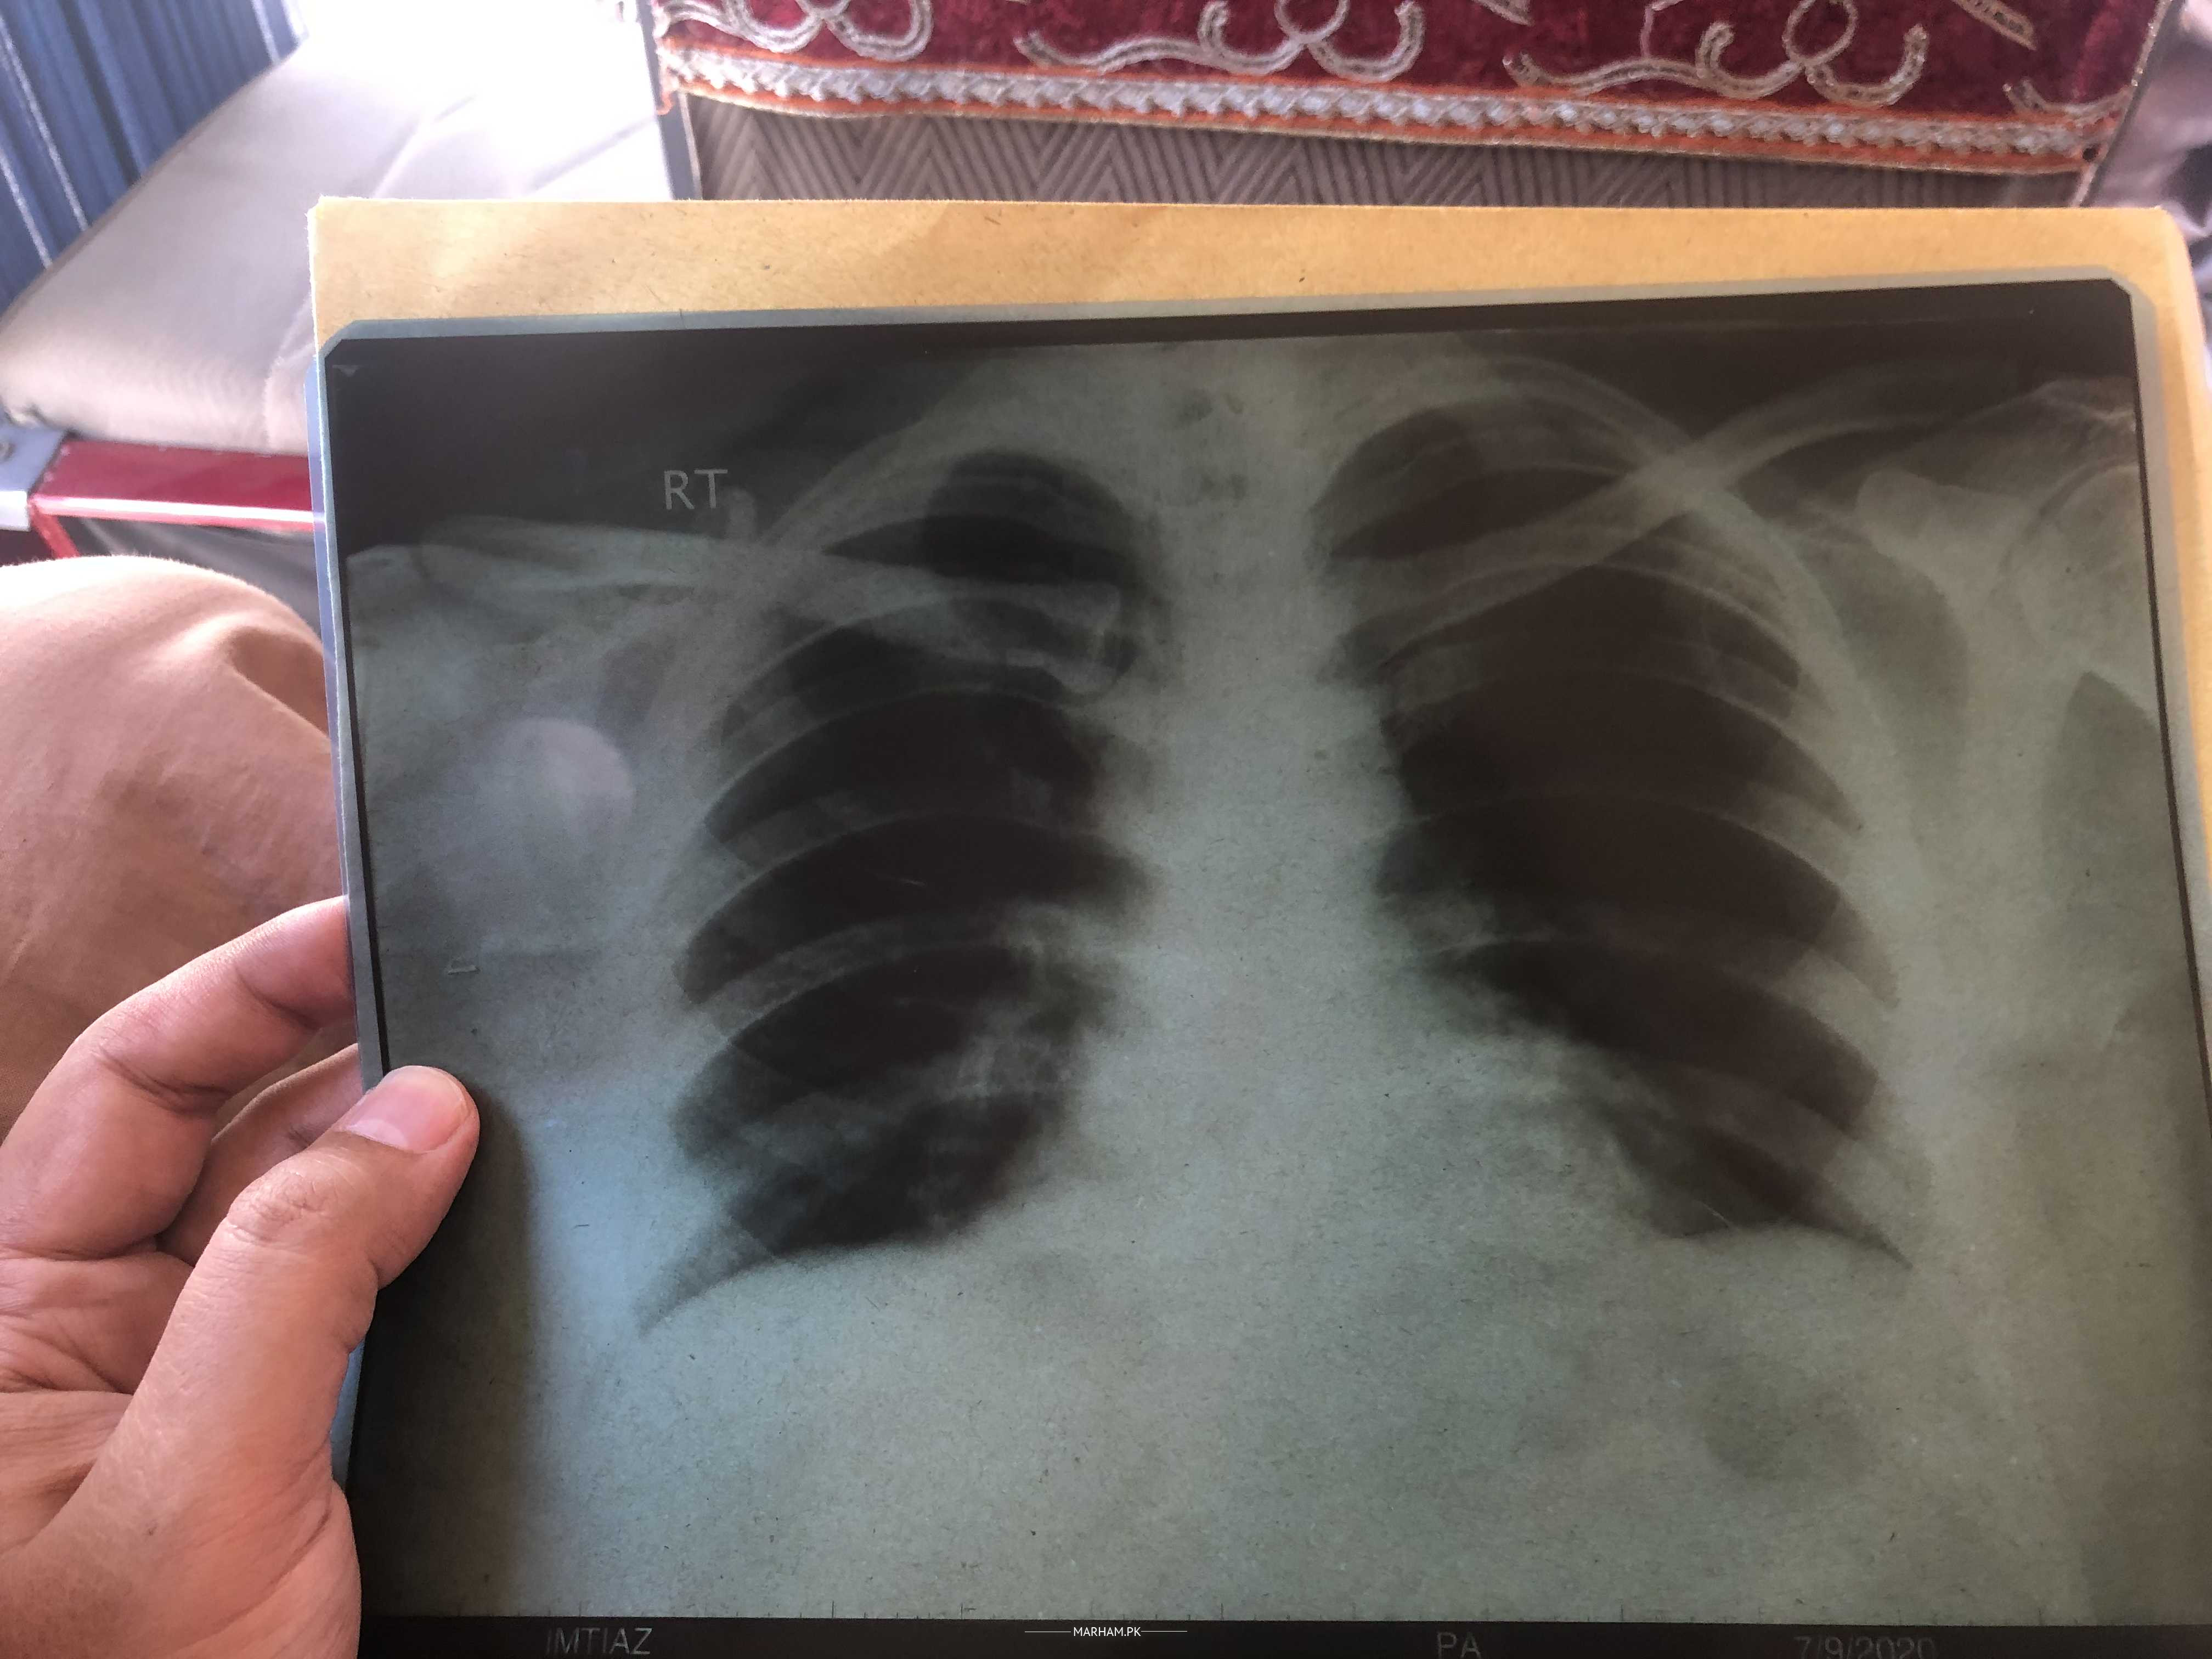

Can someone please review my lungs xray. I had flu 4 days back and I am 80% recovered from flu. Just need an opinion on safe side

Hi !your xray chest is look like normal in picture.

AOA! It’s not a good quality x ray maybe due to wrong position. If you are suspecting COVID ,As long as lung field are concerned it appears to worry.